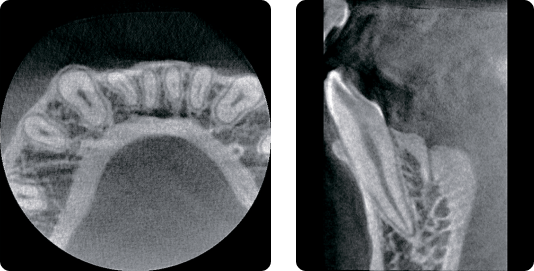

Сверхвысокое разрешение

Когда вам нужна очень точная детализация…

До 70 мкм режим сканирования для эндодонтии.

КТ-изображение с высоким разрешением в определённой области.

Выполняйте больше процедур за меньшее время.